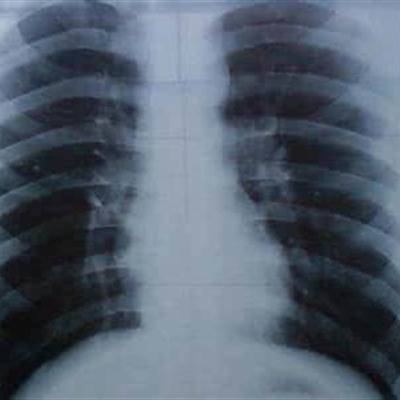

Lung shadow refers to the high-density shadow area in the lung on X-ray. There are many reasons for lung shadow, such as tumor, tuberculosis, pulmonary infection, or patients often smoking. No matter what kind of cause, if not treated in time, it will cause serious consequences, such as lung cancer, life-threatening, have to prevent. So what are the causes of the shadow in the lungs? Let's talk about it now.

Second: lung shadow does not necessarily mean lung cancer, such as long-term smokers, lung shadow will appear. So even if it appears, don't panic. At present, the most likely cause of lung shadow is tuberculosis or tumor, patients will have dyspnea, cough, fever and other symptoms.